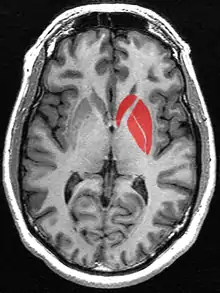

![]() Putamen (in red) shown within the brain | |